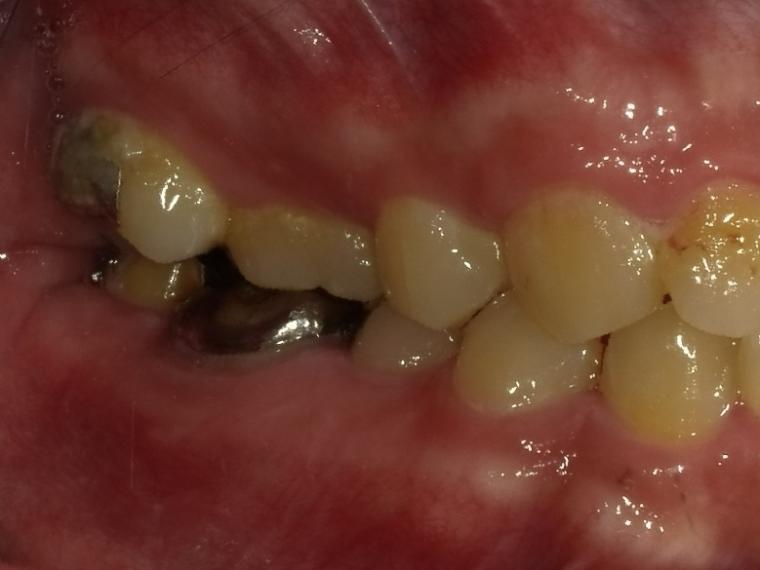

BEFORE

38歳男性/下1本欠損/インプラント埋込手術

右下奥歯が虫歯になってしまった為治療をすることになった患者さんです。

虫歯が進行していて、歯を保存出来なかったため歯を抜いて人工の骨を足してからインプラントを

1本埋込した患者さんです。